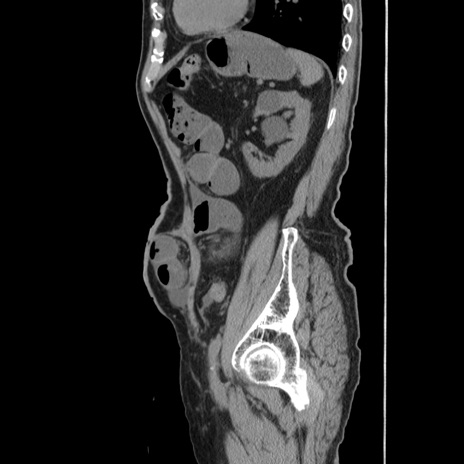

症例24(矢状断像)

【症例】80歳代男性

【主訴】左側腹部痛、嘔吐

【現病歴】本日早朝より左腹部に痛みあり。昼頃嘔吐認めたため、救急要請。

【既往歴】直腸癌(Mile手術)、胆摘

【身体所見】意識清明、BT 35.9℃、BP 221/93mmHg、SpO2 97%(RA) 、腹部:左ストーマ周囲に限局性の腹部膨隆あり。 膨隆部自発痛・圧痛あり・軟。

【データ】WBC 7700、CRP 0.09